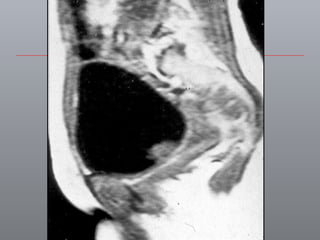

Câncer de Bexiga Estudos de imagens Diagnóstico Ultrassonografia Urografia excretora Estadiamento CT RNM Rx tórax  Cistoscopia + biópsia + biópsias randomizadas

ENDOMETRIOSE VESICAL